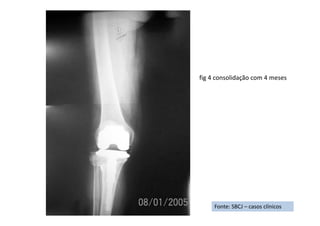

estabilidade boa em todas as direções e mobilidade de zero a 110 graus no joelho. Sete anos de segmento

Resultado Final: Atualmente apresenta marcha boa, sem claudicações nem instabilidades. Pratica caminhada

em trilhas, sem queixas em relação ao joelho, chegou a praticar boxe por um período. Os testes para

estabilidade são como se segue: Gaveta posterior negativa, gaveta anterior uma cruz em quatro, stress em varo

negativo, stress em valgo uma cruz em quatro.